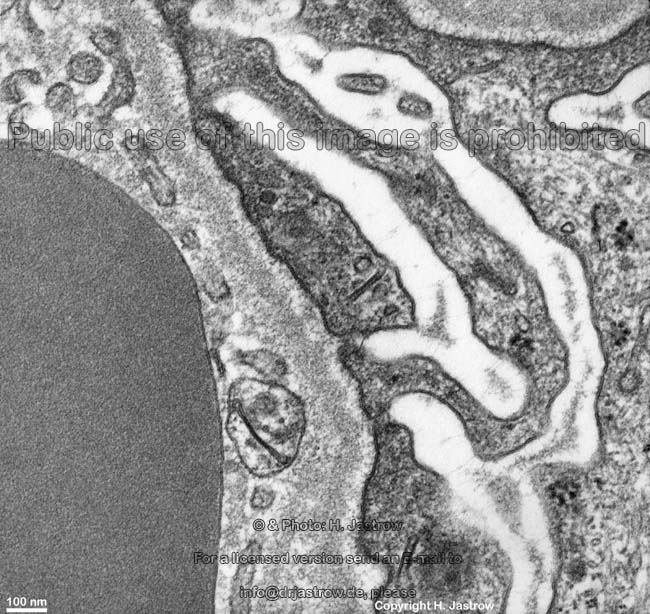

Miniaturbildübersicht Zwischenzellraum (Spatium intercellulare):

geschlängelter IZR durch

verzahnte Epithelzellen

im Pankreasgang (Ratte)

Der Zwischenzellraum, Interzellularraum (Interstitium; Terminologia histologica: Spatium intercellulare, englisch: intercellular space) ist der Raum zwischen ZellenMan spricht im Epithelgewebe wegen der Enge des Zwischenzellraumes auch von Interzellularspalt. Er wird gewissermaßen von den Außenmembranen von Zellen begrenzt. Im Epithelgewebe ist er zumeist flüssigkeitsgefüllt und daher kaum elektronendicht. Die Weite des Raumes beträgt hier etwa 25 bis 30 nm. Der Zwischenzellraum wird im Bereich von einigen Zell-Zell-Verbindungen von Epithelzellen von Interzellularsubstanz ausgefüllt (Macula und Zonula ahhaerens). In den Tight-junctions (Zonulae occludentes) ist er fast unsichtbar eng wo die in benachbarter Zellmembranen eingelagerten Occludine einander berühren fehlt er ganz, dennoch ist zwischen diesen nur punktartigen Berührungsstellen noch etwas Platz. Diese als Poren bezeichneten freien Bereiche sind für den Durchtritt von Wasser und kleinen Ionen besonders im Darm wichtigen parazellulären Transport wichtig: im Duodenum und Jejunum sind die Poren 0,8 nm weit, hier wird ca. 60 % des Wassers dem Nahrungsbrei entzogen, im Ileum sind die Poren nur noch 0,4 nm weit, hier werden noch 20 % des Restwassers entzogen und im Colon beträgt die Porenweite nur noch 0,23 nm, wodurch nochmals ca. 20 % des verbliebenen Wassers entzogen werden können.

Insbesondere im Bindegewebe wird der Interzellularraum sehr weit und ist mit Interzellularsubstanz bestehend aus Fasern (Kollagenfasern, elastische Fasern, retikuläre Fasern) sowie Grundsubstanz ausgefüllt. Im Nervengewebe findet sich, wie auch im Muskelgewebe, etwas kollagenes und elastisches Fasermaterial im Interzellularraum. Abschnittsweise ist der Raum auch sehr schmal (Zentralnervensystem). Im Bereich von Synapsen und motorischen Endplatten müssen Neurotransmitter den Interzellularraum passieren.